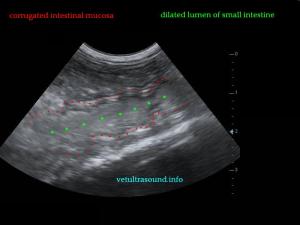

Findings: Α distention of the small intestine was noted. A corrugated small intestinal loop was found (pic1), which led to an acoustic shadow (pic2-3). This was because of an intraluminal foreign body, which was causing a partial obstruction of the small intestine.

Ευρήματα: Διάταση του πεπτικού σωλήνα με αφθονία υγρών και αέρα. Βρέθηκε τμήμα του λεπτού εντέρου με έντονη πτύχωση του βλεννογόνου του (pic1) και παρουσία πιθανού ενδοαυλικού ξένου σώματος το οποίο δημιουργούσε μερική στένωση του εντέρου και ακουστική σκιά πέραν αυτού (pic2-3).